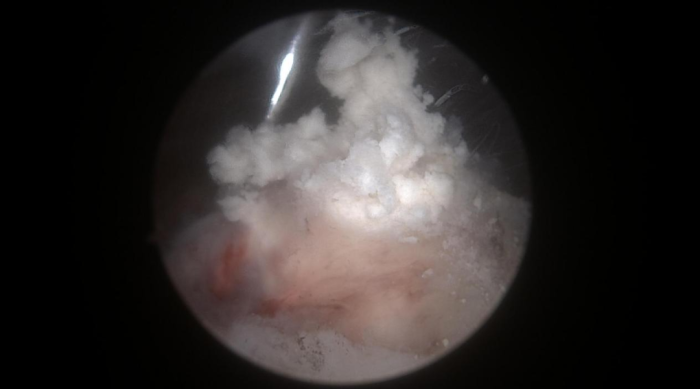

门诊医生立即为黄阿姨办理了住院,并于当天晚上完成急诊手术,通过3个0.5cm小切口在关节镜下解决了病因。镜下可见冈上肌腱内冒出牙膏状钙化沉积物,彻底清理后缝合肩袖破口。